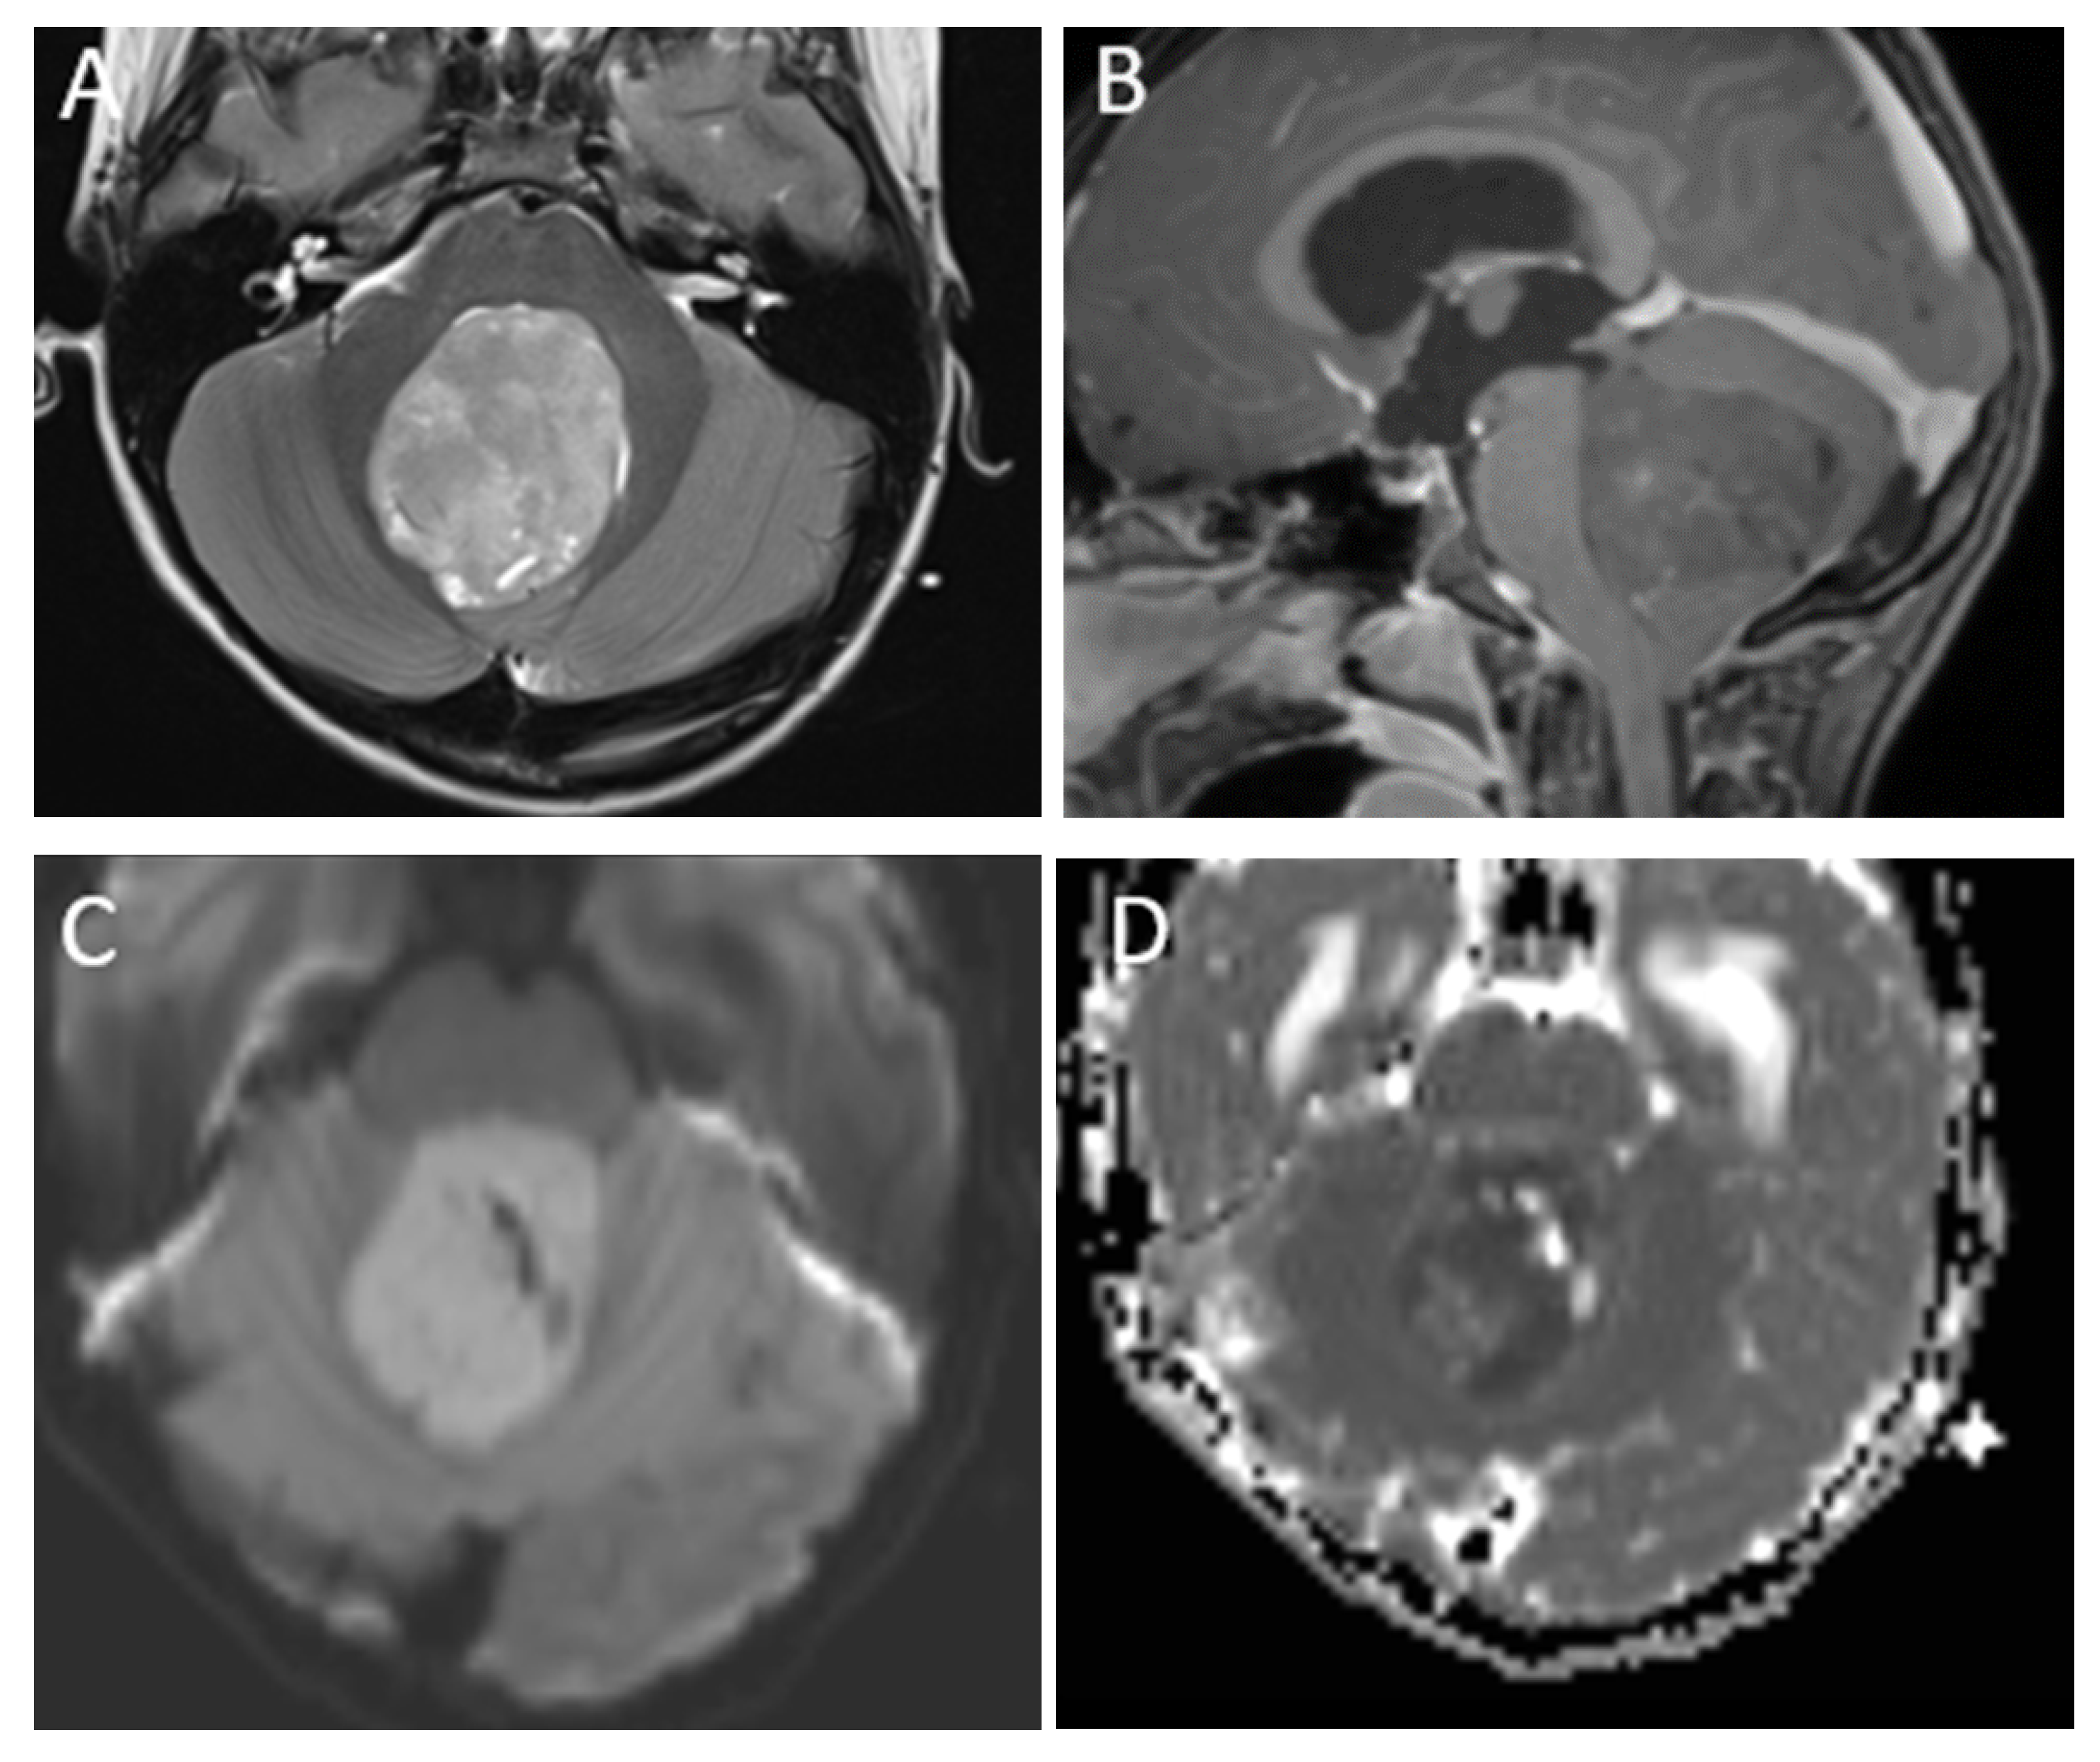

| Medulloblastoma | Exclusively posterior fossa Most commonly in fourth ventricle/cerebellar vermis (non-WNT, non-SHH, or WNT), can involve cerebellopontine angle (WNT) or cerebellar hemispheres with extra-axial extension (SHH) | Diffusion restricting Variable enhancement Cystic/necrotic change may be present Calcifications uncommon Taurine peak characteristic |